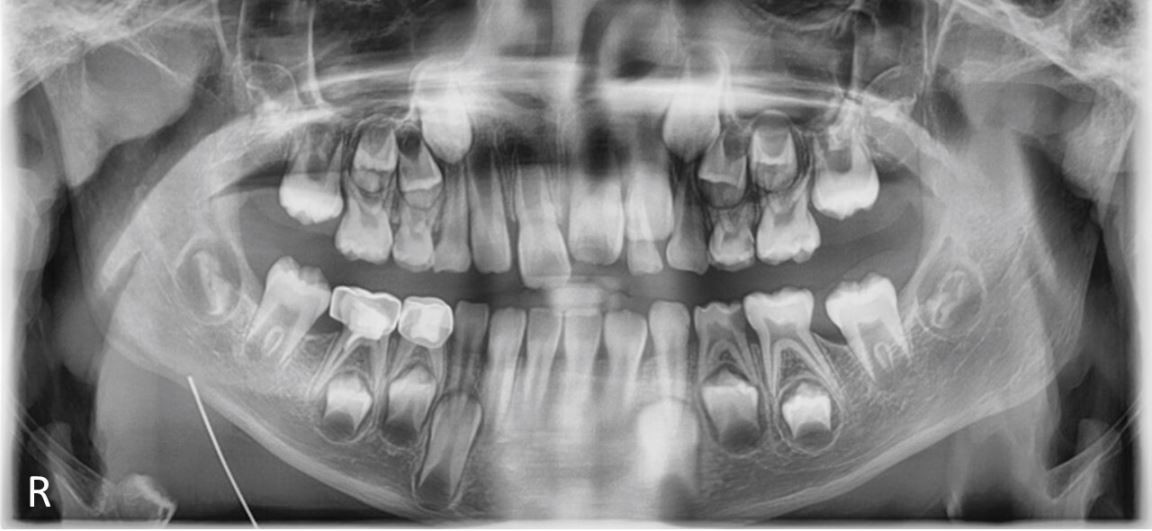

Panoramic radiograph after eight months follow-up showing progression of first permanent molar development with initial eruption evident and second molar crypts becoming visible